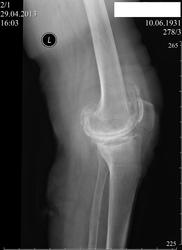

Пациентка 81 года, в анамнезе 45 лет назад, грубая травма колена ( упала с мотоцикла при движении последнего),накануне повторная травма коленного сустава (падение на колено) .Как описать находки на R -грамме и что является субстратом изменений?

ДОА 3.Резкое сужение суставной щели, грубые остеофиты.

+ пателло-феморальный артроз, + хондроматозные тела в верхнем завороте, +, конечно, остеопороз. Под стрелкой место не нравится на предмет краевого перелома экзостоза. А упала снова с мотоцикла?)))

Мне бы то же было бы интересно, но пока других мнений нет. Может быть, вы правы, как альтернатива вашей версии- метаплазия внутирисуставных мягких тканей в костную ткань, но у меня нет опыта в этом вопросе.

Сегодня разговаривал с дочерью пациентки ( она наша рентгенолаборант) , с её слов всё нормально, мать ходит; я полагаю, что если бы был перелом экзостоза- это едва ли было бы возможно.